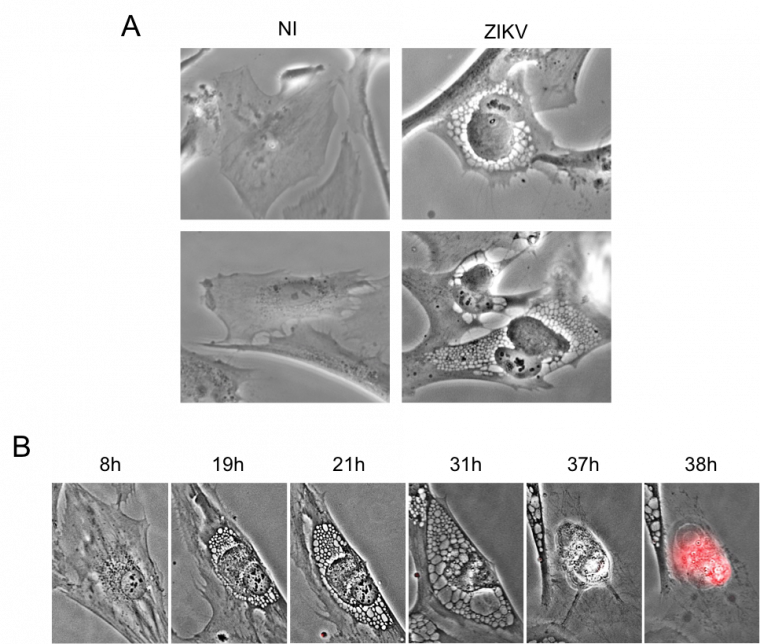

Nous avons étudié l’effet cytopathique du virus, plus précisément les changements morphologiques des cellules lorsque le virus se multiplie. Pour cela nous avons infecté des cellules épithéliales humaines avec une souche de virus Zika et nous les avons filmées par vidéo-microscopie. Nous montrons qu’ une cellule infectée réagit en formant de grosses vacuoles qui vont aboutir à l’implosion et la mort de la cellule (Figure 5A). Pour faciliter la visualisation, les cellules saines sont colorées en vert et lorsqu’elles meurent elles deviennent rouges. Avec ce système, nous pouvons alors quantifier le signal rouge qui représente la mort cellulaire induite par le virus. Nous nous intéressons également aux facteurs de restriction qui sont des protéines cellulaires à activité antivirale servant à protéger la cellule contre l’infection de différents virus. Parmi les facteurs de restriction étudiés, nous avons observé que l’absence d’une des protéines IFITM (Interferon – Induced Transmembrane) nommée IFITM3, permettait au virus Zika d’accéder au cytoplasme des cellules et d’y induire la formation de vacuoles menant à la mort cellulaire (Figure 5B).

Nous avons observé ces effets cytopathiques du virus Zika dans différents types de cellules humaines : cellules épithéliales (cellules qui constituent les épithéliums, tissus marquant la limite entre l’organisme et son environnement : peau, épithélium intestinal, pulmonaire, etc.), fibroblastes cutanés (sûrement une des premières cibles du virus au niveau de la peau après la piqûre par le moustique) et également dans les astrocytes, des cellules du système nerveux central (Figure 6). Le virus Zika, comme nous l’avons mentionné précédemment, provoque des perturbations et des maladies neurologiques. Par conséquent, comprendre comment le virus infecte, perturbe et détruit les cellules du cerveau est primordial.

A. Des astrocytes ont été infectés par le virus Zika et observés au microscope 24 h plus tard. NI : cellules non infectées ; ZIKV : cellules infectées par le virus Zika. B. Des fibroblastes de peau ont été infectés avec le virus Zika et filmés pendant une quarantaine d’heures. Une fois morte, la cellule devient rouge.